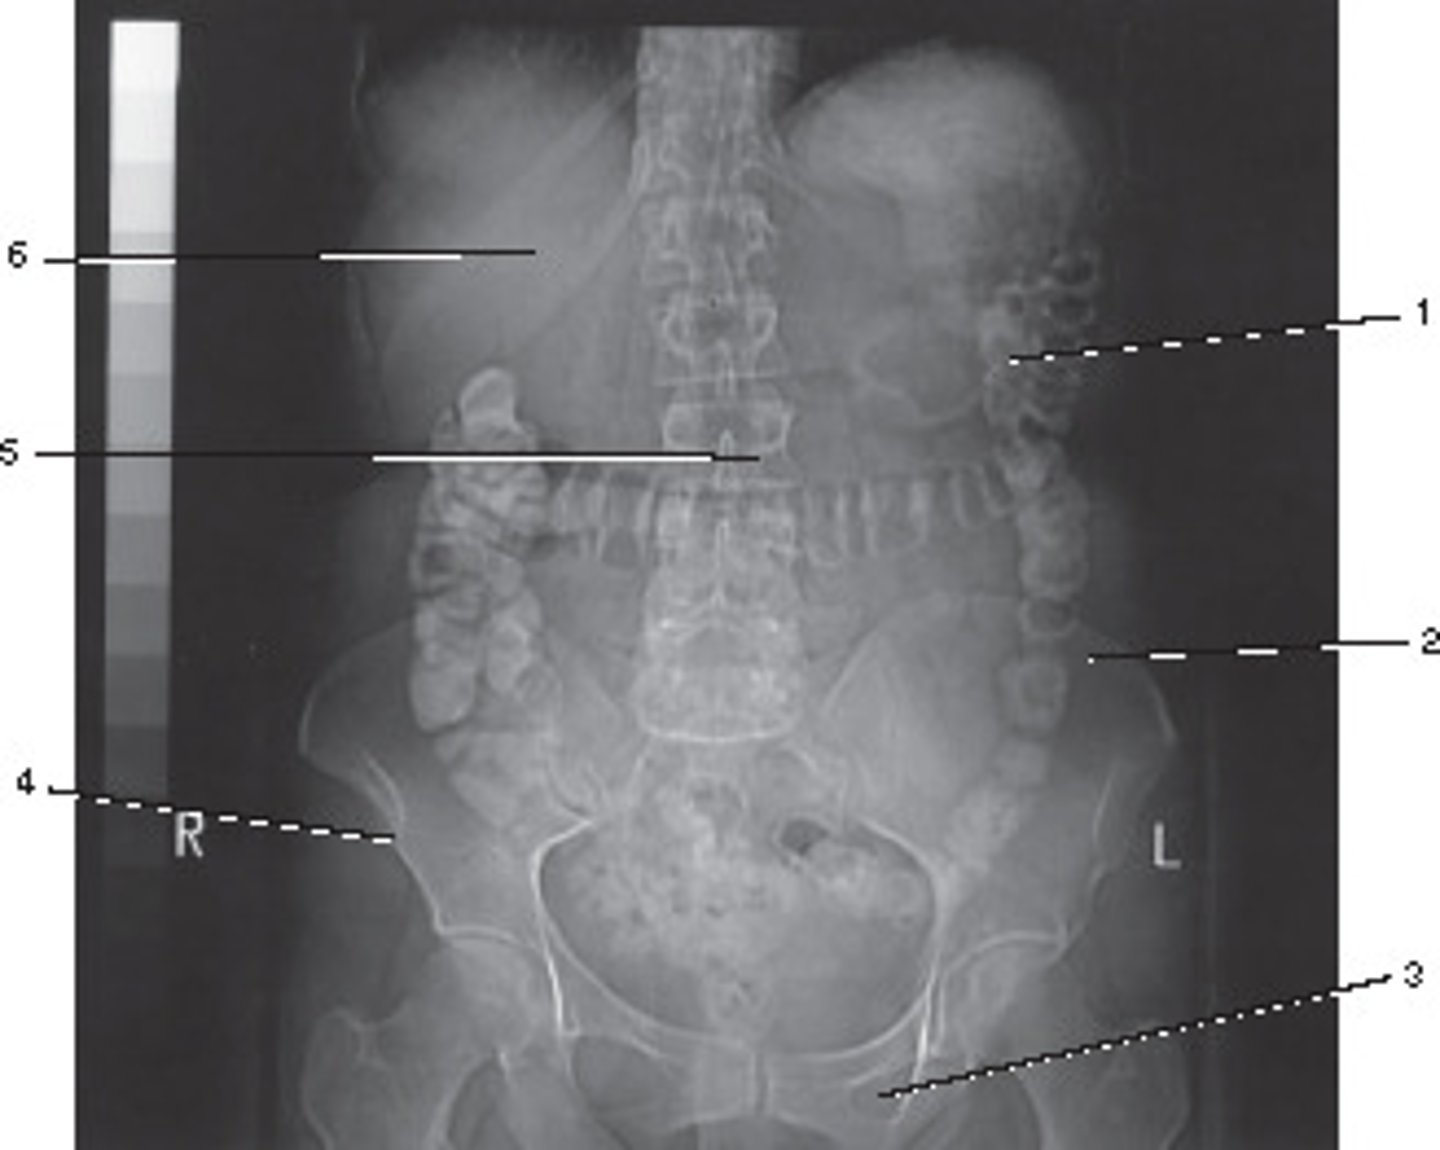

Abdomen and Adomen/Pelvis

This localizer (scanogram) could be used to program which of the following examinations?

<p>This localizer (scanogram) could be used to program which of the following examinations?</p>

74

New cards

0 degrees;

The Azimuth setting refers to the relationship betyween the x-ray tube and detectors during scout of localizer production.

What azimuth setting was used to obtain this image?

<p>What azimuth setting was used to obtain this image?</p>